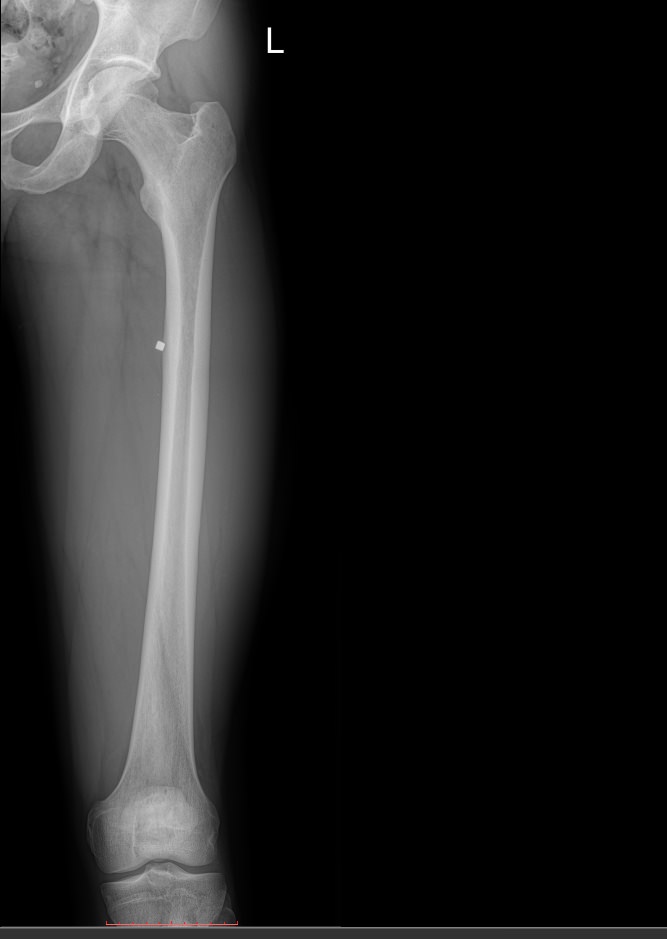

Обследование бедренной кости чаще всего выполняют рентгеновским методом. Это неинвазивный, безболезненный, высокоинформативный и доступный способ получения информации о состоянии и структуре костной ткани. Проходя через тело, рентгеновское излучение больше всего задерживается в самых плотных образования – костных, поэтому на классическом негативном снимке их изображения самые светлые. Патологические изменения, развивающихся здесь, также ясно видны. При их выявлении врач принимает решение о дополнительных видах диагностики и выбирает способы лечения.

• Состояние костной ткани и надкостницы: участки гнойного воспаления, разрежения, размягчения, деструкции, склерозирования, развития опухоли и кистозных образований;

• Изменения в мягких тканях: обызвествление, воспаление, опухоль;

• Целостность кости: свежие переломы, костные мозоли, ложные суставы.В заключении врач описывает преимущественно патологические изменения или пишет, что таких не обнаружено.